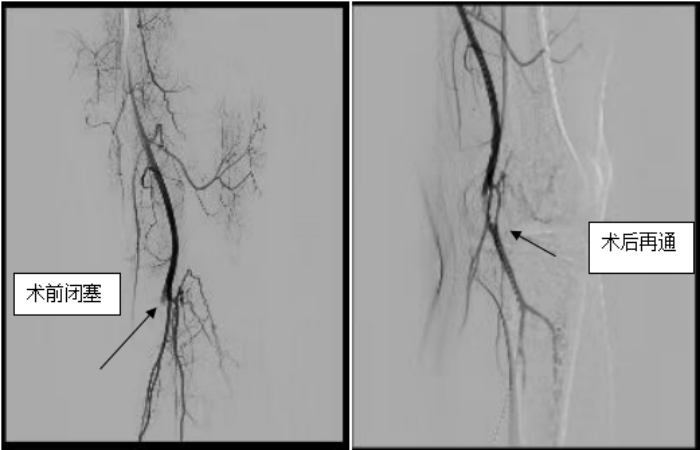

云中二院讯(通讯员 李江龙)2023年2月13日,医院神经-心血管科为一名22岁小伙子成功完成下肢动脉闭塞再通术。

22岁小伙子平时喜欢久坐玩游戏,且经常跷“二郎腿(左脚在上)”。2月前发现左下肢疼痛、麻木、发凉,行走1公里或者跑步数十米即出现上述症状,休息后缓解,在外院行下肢血管CTA检查示:左侧腘动脉闭塞,口服药物治疗无缓解而入住我院。行相关检查排外心源性栓塞及血管炎等因素后,经专家团队充分讨论,给予行左侧闭塞腘动脉介入治疗,使用导丝通过闭塞段血管后行球囊扩张成形术,手术顺利,术后血流恢复好,间歇性跛行症状明显改善。